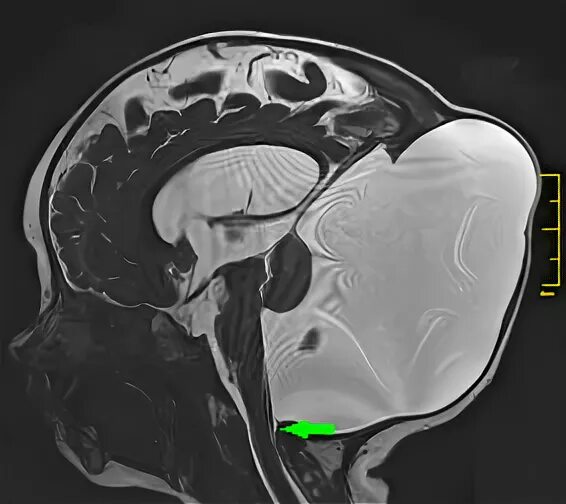

Денди уокер у взрослых